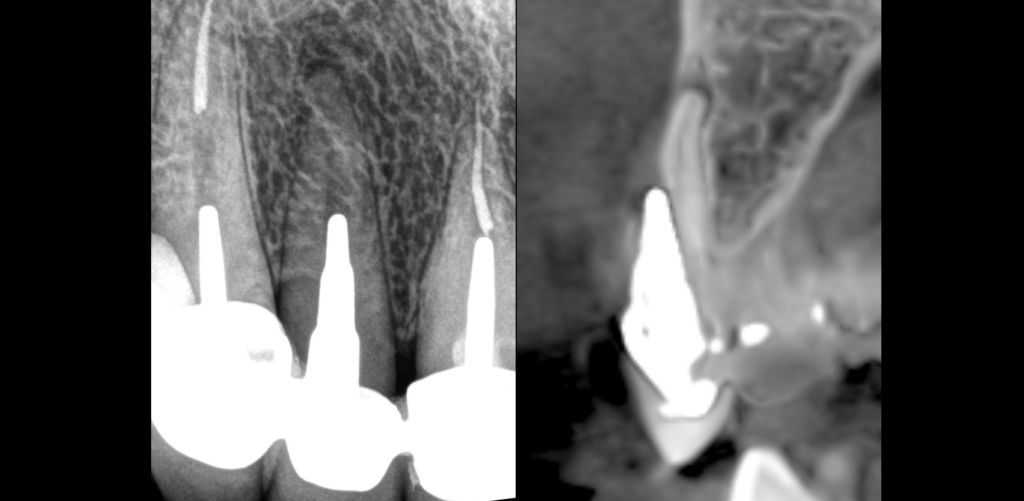

🦷 𝐐𝐮𝐞𝐥𝐬 𝐬𝐨𝐧𝐭 𝐥𝐞𝐬 𝐞́𝐥𝐞́𝐦𝐞𝐧𝐭𝐬 𝐫𝐚𝐝𝐢𝐨𝐠𝐫𝐚𝐩𝐡𝐢𝐪𝐮𝐞𝐬 𝐫𝐞𝐦𝐚𝐫𝐪𝐮𝐚𝐛𝐥𝐞𝐬 𝐜𝐨𝐧𝐜𝐞𝐫𝐧𝐚𝐧𝐭 𝐜𝐞𝐭𝐭𝐞 𝐝𝐞𝐧𝐭 𝐧°𝟏𝟐 ?

📌 Une perforation de l’ancrage corono-radiculaire au niveau du 𝟏/𝟑 𝐦𝐞́𝐝𝐢𝐚𝐧 𝐞𝐧 𝐯𝐞𝐬𝐭𝐢𝐛𝐮𝐥𝐚𝐢𝐫𝐞

📌 Une lésion apicale